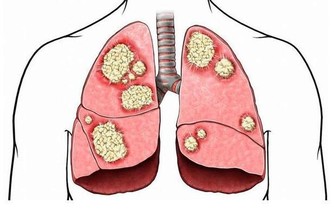

經過一個夜晚的睡眠,在呼吸和出汗的同時,身體中的水分發生了流失而且血液濃度也會變稠,這也是早晨心腦血管疾病高發的原因。此時喝上一杯溫開水,就能夠補充水分,降低血液濃度,對人體健康是很有幫助的。

不吃早餐最直接的就是會傷害胃部健康。經過一夜的分解、消化,此時的胃酸濃度很高,而如果不吃早餐,飢餓就會使得胃酸持續分泌長期不吃早餐會造成胃酸持續傷害胃黏膜,很容易出現胃炎、胃潰瘍等腸胃疾病。